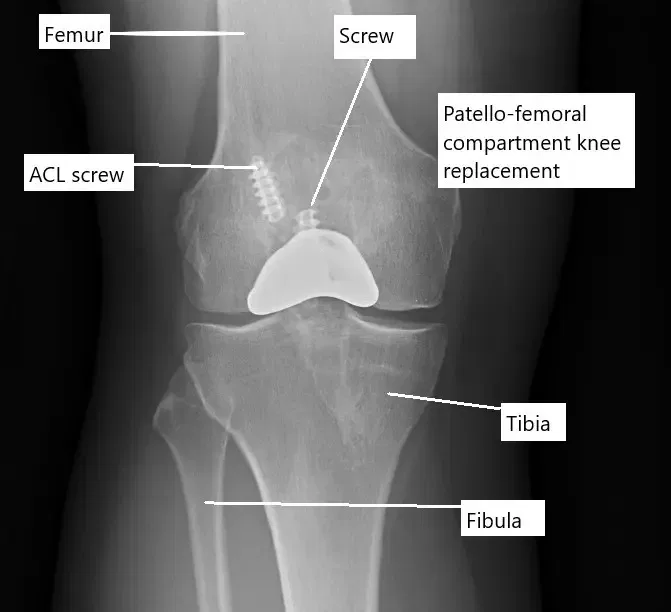

X-ray showing a partial knee replacement.

The knee joint has three compartments: the inner (medial), outer (lateral), and front (patellofemoral). Healthy cartilage covers the bones and allows smooth movement. Ligaments, the meniscus, and surrounding muscles help stabilize the joint. When cartilage and bone wear down, the joint becomes painful and may lose its normal motion.